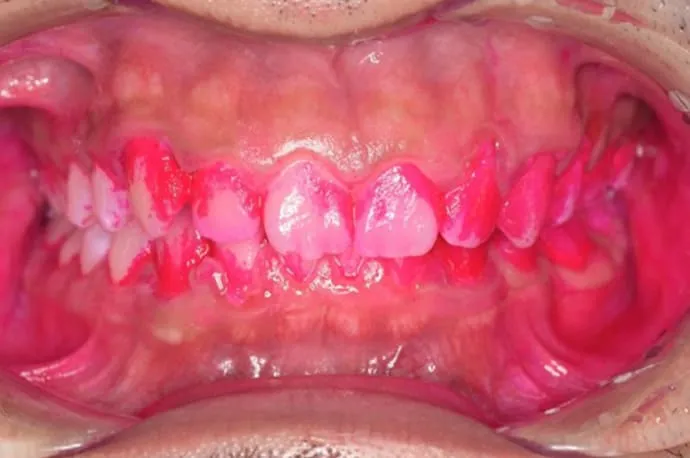

歯磨き指導例

治療前

治療後

こちらの画像は、ブラッシング前後の染め出しの画像です。汚れがついている部位は濃くピンクに染まります。1回の歯磨き指導でも、汚れの付着が大きく減っていることが確認できます。ぜひ一度、高輪の歯医者「TAKANAWA GATEWAY Clinics 歯科・矯正歯科」へご来院いただき、自己流の歯磨きから卒業してみませんか?